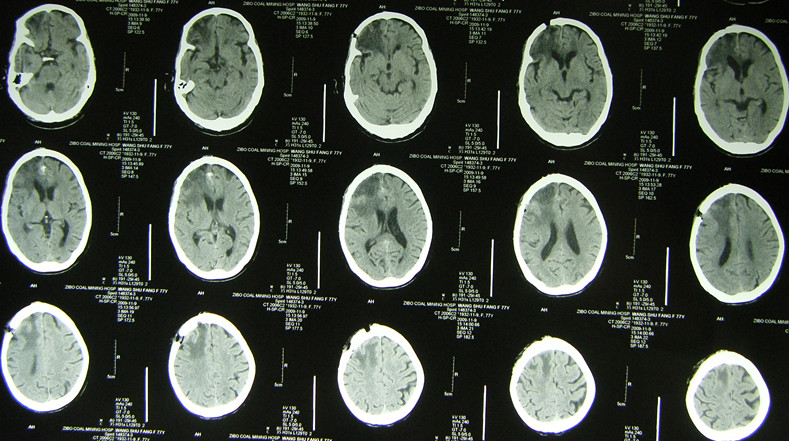

(1)注意识别脑瘤卒中的平扫CT及 MIR片特点:①多为形态不规则密度不均匀的混杂密度病灶,而高血压脑出血多为密度较均匀的类圆形团块状较高密度灶;② 病灶常位于远离中线的脑叶,而高血压脑出血的病灶常位于基底节区及丘脑区;③ 其病灶相对于高血压脑出血病灶的周围水肿比较明显,出血灶周围常有较广泛的大片脑水肿低密度区,而一般脑血肿周围常仅有薄的水肿带;见影像片1,2

影像片1:CT平扫,示形态不规则密度不均匀的混杂密度病灶,位于枕叶及侧脑室枕角处,局部水肿明显。

影像片2:CT及MR比较